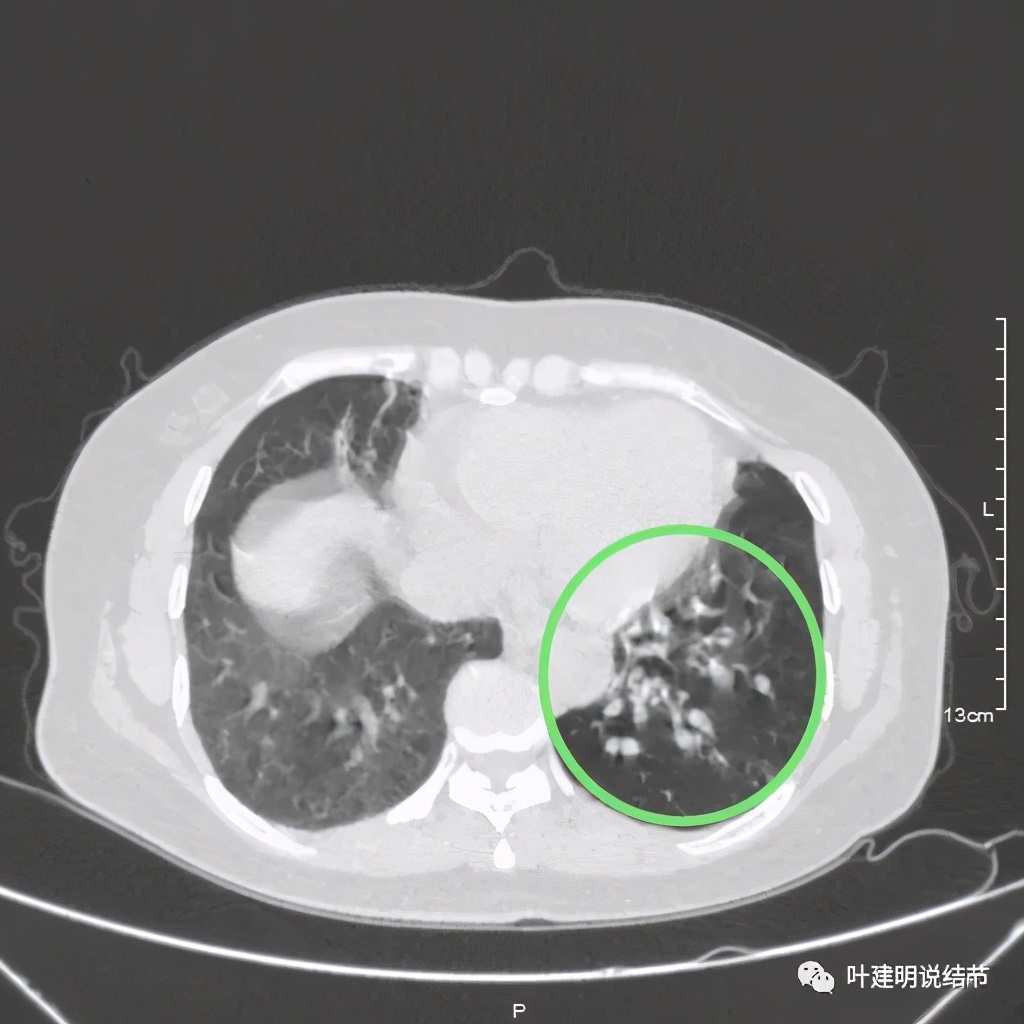

可见同样部位的左下结节已经较去年密度明显低了一些,说明有所吸收了!基本上已经只是磨玻璃密度了。那么其他病灶的情况呢?

也是有所变化,但病灶仍仍在,是异常的。最后这同图上还见到似乎也是实性伴小空腔的病灶(红色三角形标注处),是不是与之前的病灶有点像?